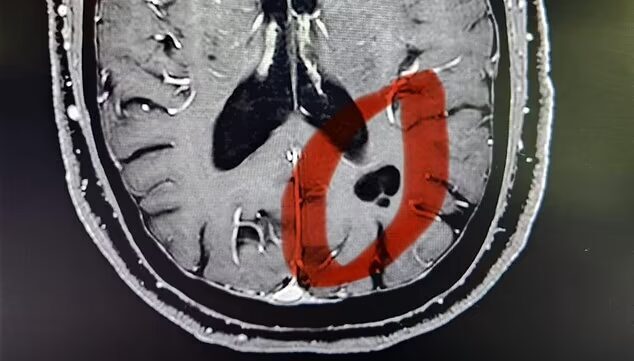

11月6日放映の「ノンストップ」(フジテレビ)は、10月27日付のイギリス紙『デイリー・メール』の報道を引用する形で、MRI検査の結果ユリ・ゲラーの超能力の秘密が明らかになったと紹介。MRI検査の結果、ユリ・ゲラーの脳に、普通の人にはない黒い影が発見された。ゲラー本人によればそれは宇宙人にインプラントされたもので、6歳の時遊んでいて、直径3メートルの球体から光線を額に浴びせられ、それから超能力を発揮し始めたという。川崎中央クリニックの市村真也院長によれば、この場所は後頭葉と頭頂葉の中間にあり、現代の技術ではこの場所に何かをインプラントすることは不可能だという。